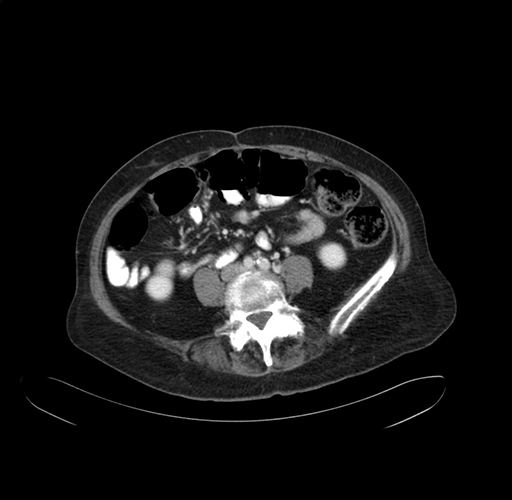

Axial Venous